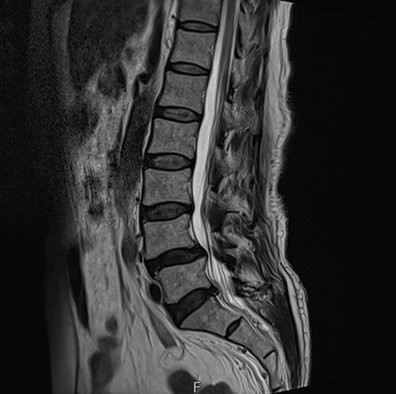

그림5.png 촬영 일시: 2025.05.02

[병변에 직접 치료하고 있는 CI 주사치료 영상입니다 ^^ C-arm 장비를 통해 아픈 곳에 정확히 약물을 주입하는 방식이기 때문에 환자분들 만족도가 높은 시술 중 하나죠!]